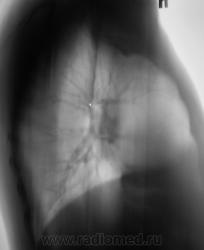

Я тоже сначала подумал о "периферическом", но похоже, "обломался". Сейчас добавлю боковые томограммы.

Сейчас добавлю томограммы в прямой проекции.

На томограммах не получили изображение округлой тени. Возможно, она имеет отношение к грудной стенке?

С Вашей точки зрения на боковх ТГ разве тень вне легочного поля? А что на срединных срезах справа паратрахеально?

Верхняя полая вена...да и эта тень медиальнее, чем та, с которой, вероятнее всего, работал автор случая...как мне кажется...

Если мне не изменяет память, в/полая вена так высоко "не забирается", образуясь от слияния плечеголовных вен чуть ниже уровня 1-го реберного хряща.